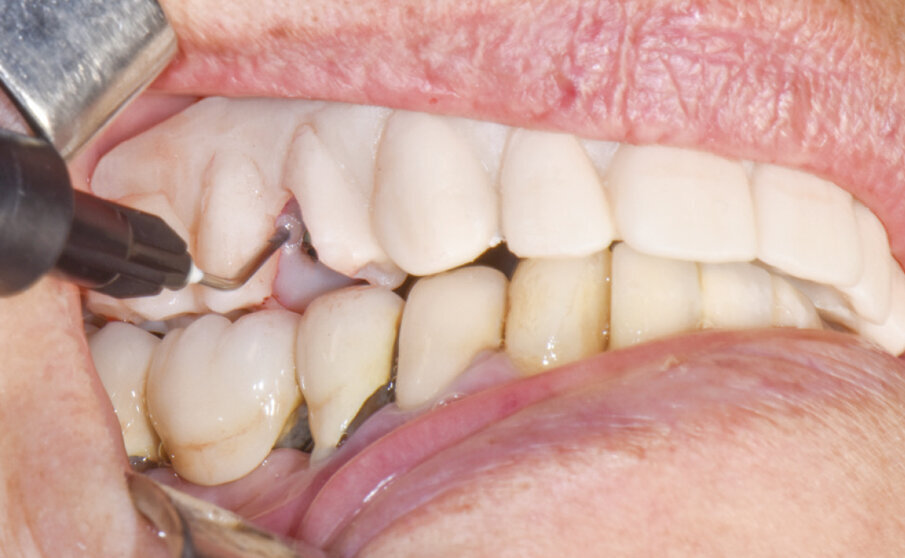

Si scelgono quindi i monconi MUA con i GH e gli angoli di compensazione adeguati per il raggiungimento del miglior parallelismo. Il posizionamento dei MUA viene eseguito con l’ausilio di viti polifunzionali che permettono di visionare e confermare il parallelismo di emergenza. Dopo aver stabilito la posizione, i MUA vengono battuti con un percussore con punta in PEEK secondo l’asse implantare, attivando così la connessione cono Morse. Successivamente si avvitano i cilindri da incollaggio sui coni dei MUA (Fig. 5).

Si procede successivamente alla perforazione della protesi provvisoria in resina in corrispondenza delle emergenze implantari. Si controlla che l’allettamento della protesi avvenga passivamente sui cilindri precedentemente scorciati quanto basta (Fig. 6). Si procede facendo chiudere la bocca alla paziente, in occlusione con l’arcata antagonista. A questo punto si bloccano due cilindri monolateralmente con resina composita in posizione di intercuspidazione massima (Fig. 7). Dopo questo primo fissaggio, che permette di registrare correttamente l’occlusione, vengono bloccati tutti gli altri cilindri. Si ribasano infine gli spazi vuoti della protesi provvisoria sulla sella edentula dovuti alle estrazioni.

Fig. 5 - Cilindri da incollaggio posizionati sopra i monconi MUA già definitivamente fissati negli impianti.

Fig. 6 - Adattamento e posizionamento della protesi in resina.

Fig. 7 - Controllo del rapporto occlusale e fissaggio dei cilindri alla struttura.